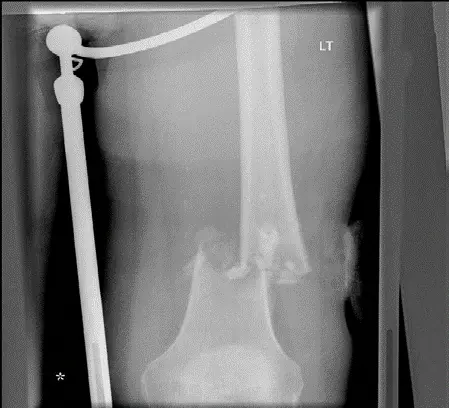

إنقاذ الأطراف مقابل البتر:

- يسعى الأستاذ الدكتور محمد هطيف دائمًا إلى تحقيق إنقاذ الطرف (Limb Salvage) كلما أمكن ذلك، مع الحفاظ على الوظيفة. يتضمن ذلك إزالة الورم وإعادة بناء العظم والمفصل باستخدام طعوم عظمية، أو مفاصل اصطناعية، أو أطراف صناعية داخلية.

- يُصبح البتر ضروريًا في حالات الأورام الكبيرة جدًا، أو التي تغلغلت بشكل واسع في الأنسجة الرخوة، أو التي أثرت على الحزمة الوعائية العصبية الرئيسية بحيث لا يمكن تحقيق هامش جراحي آمن مع إنقاذ الطرف.